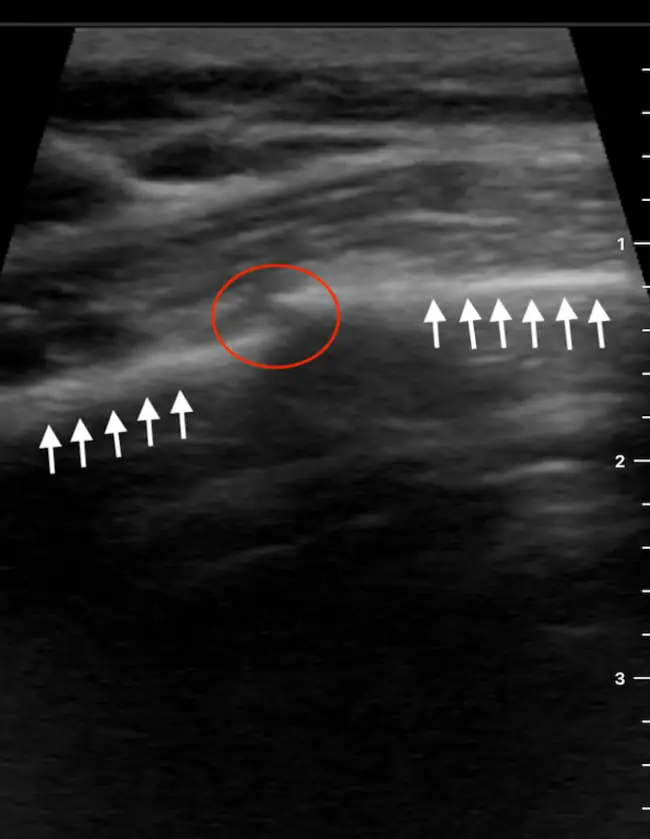

POCUS reveals a clear cortical interruption of the 4th anterior rib in the longitudinal plane. The linear hyperechoic bony cortex (white arrows) shows discontinuity with a minimal step-off (red circle) consistent with a nondisplaced rib fracture. There are no surrounding soft-tissue abnormalities, such as a hypoechoic mass suggestive of a hematoma or disruption of muscle architecture suggestive of a muscle tear.

- On a chest wall POCUS, a step-off or cortical discontinuity at the point of maximal tenderness is consistent with a rib fracture.